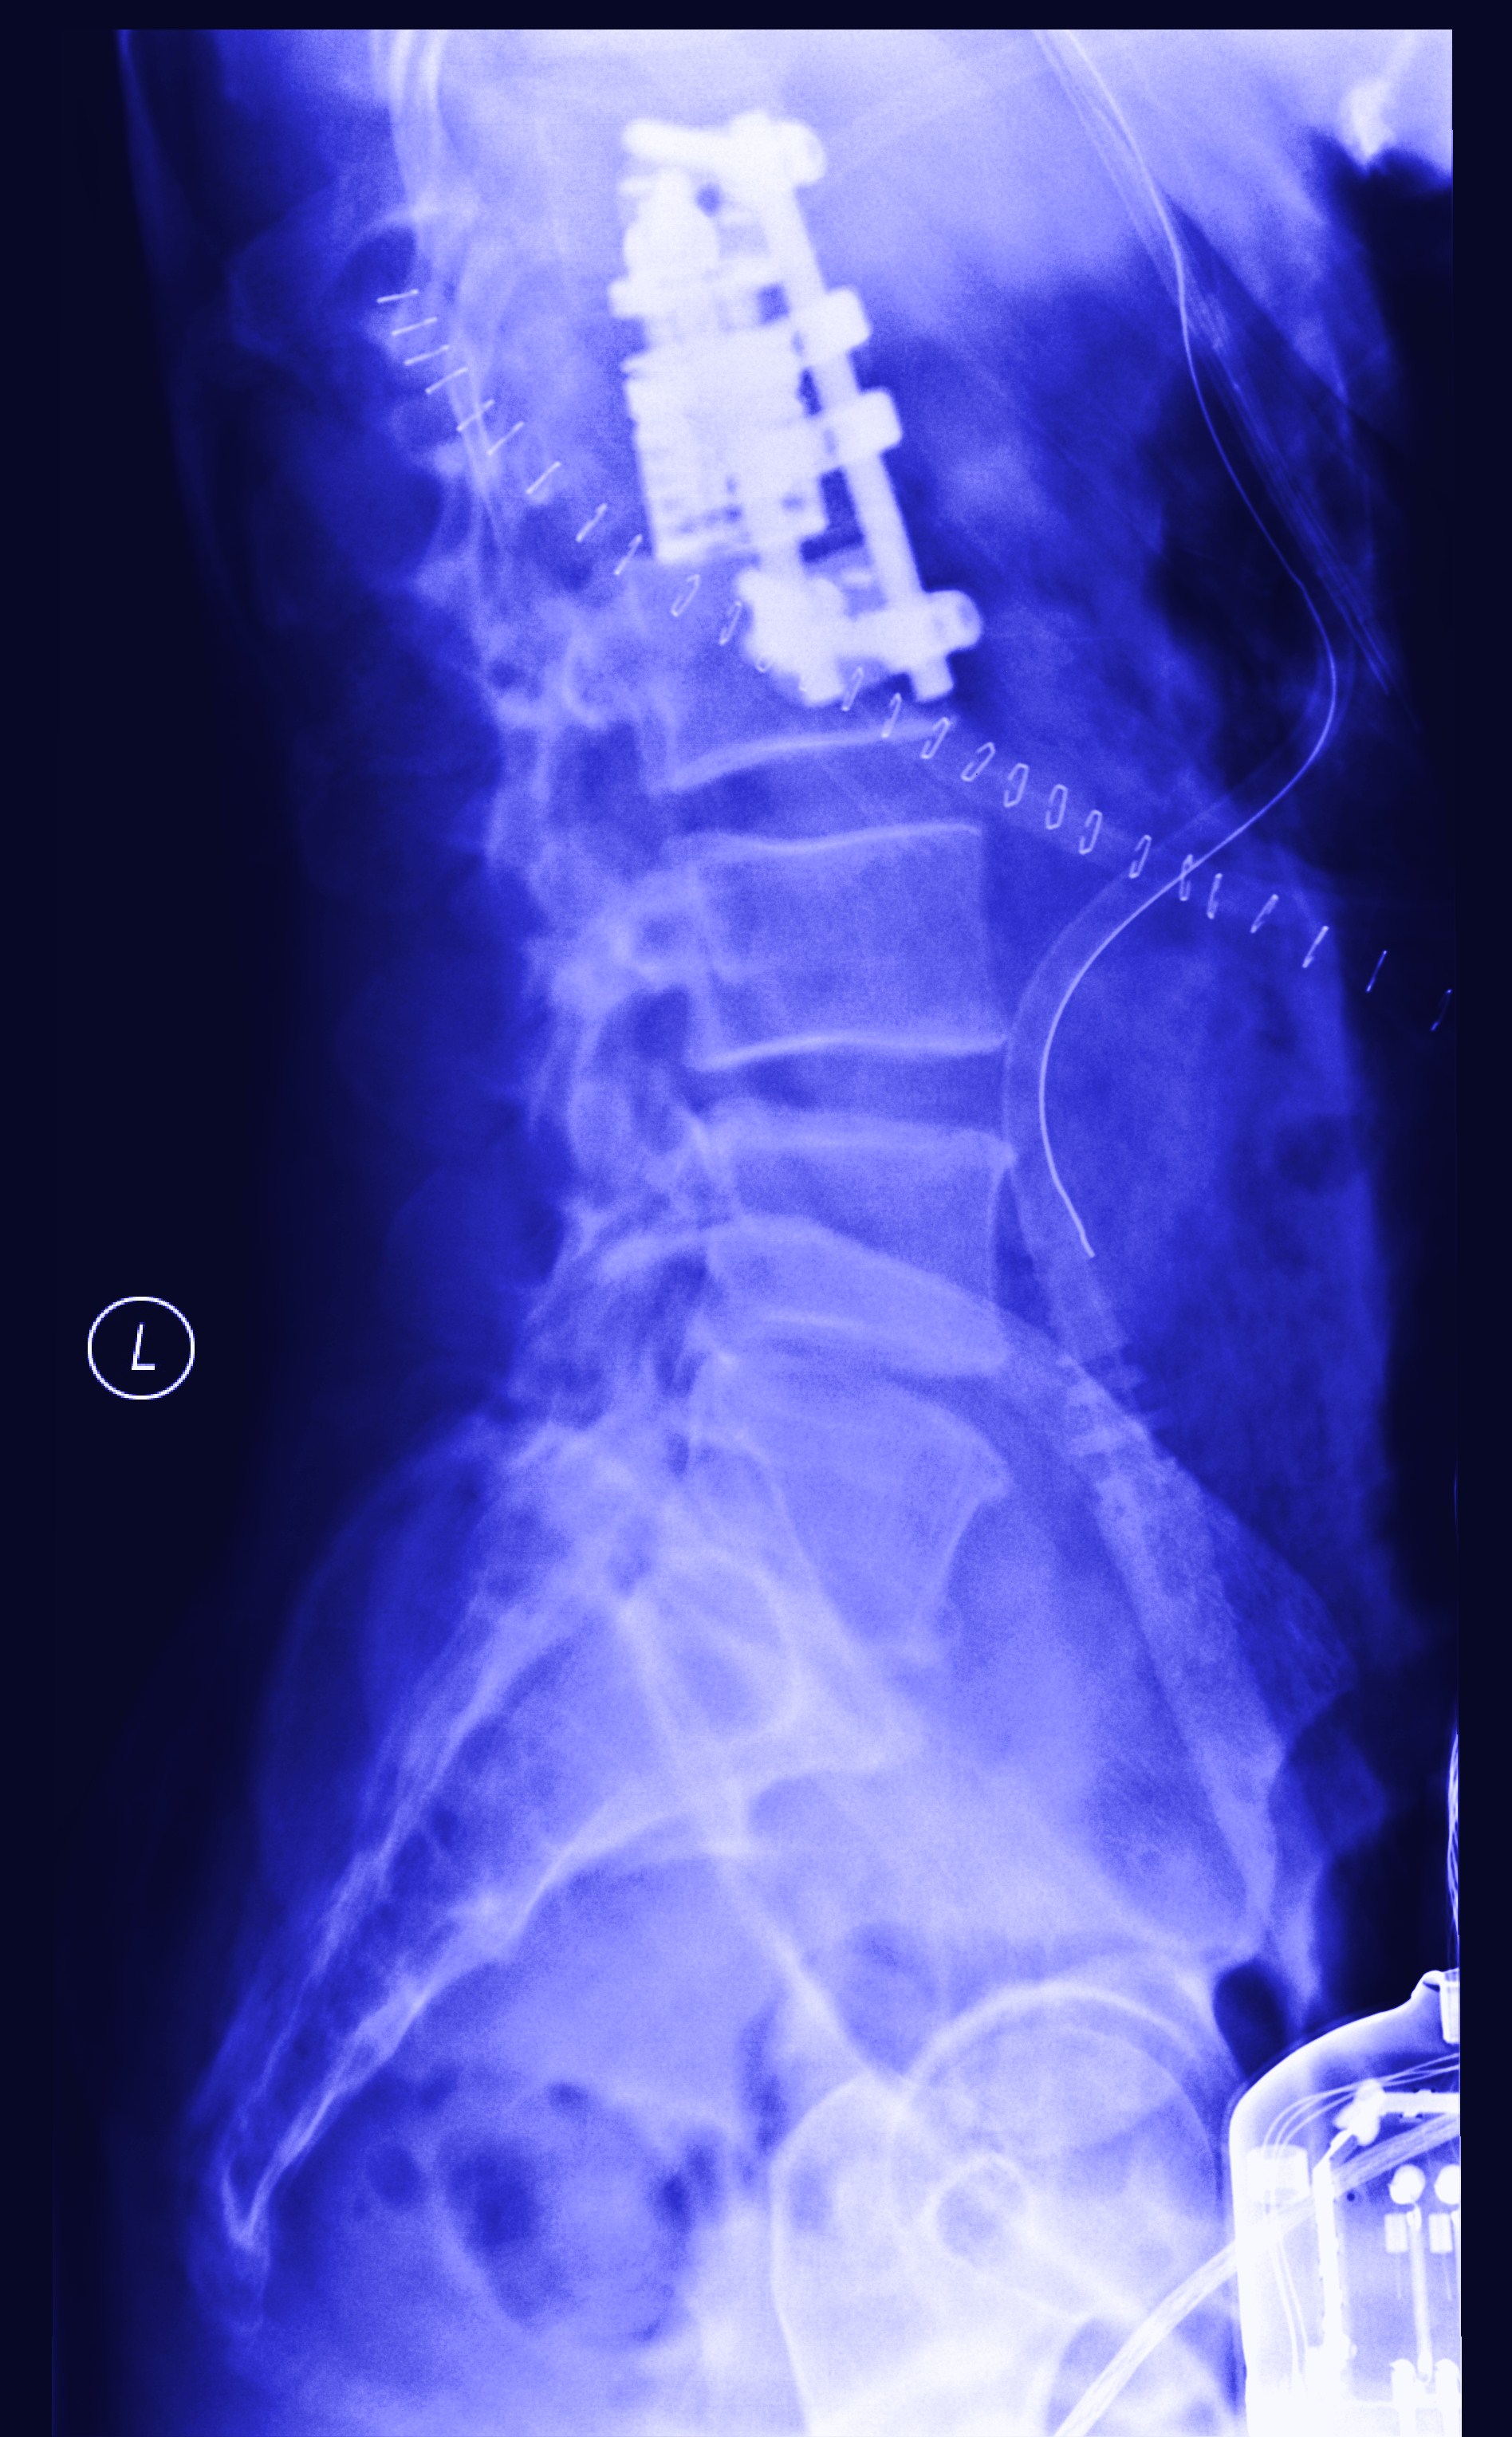

four years ago this month I fell (pretty seriously) but- I bounced.

time at this point stretched itself outup- into minute by minute segments and continued for a few months like this- there was no ‘bounce’ apparent at this point. It’s probably more like you have to crawl out of whatever crater you made on impact and you are just trying to get back to the surface-I started to keep a journal when I got out of the hospital- many many days it just says what time I got up and maybe how I felt (in like 2 or 3 words) but eventually I had entries about dressing myself and then an entry about how I would eventually stop making entries- and not to worry because I was getting better.

you are slowly on the way back- in fact once you are out of all your medical equipment- you look normal- (but you are not) you really still have a ways to go- and it can be scary- but this is part of bouncing- you end up back in the air!